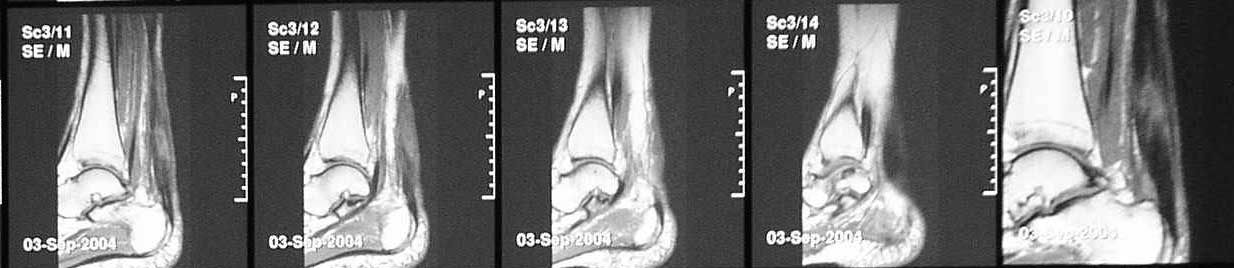

В сентябре сделана МРТ, цитирую заключение: "по внутренней поврехности сухожилия на уровне средней трети определяется очаг с неоднородной гиперинтенсивностью сигнала на T2W и изоинтенсивного сигнала T1W неправильной форму. Прротяженность очага до 43 мм в вертикальном диаметере. В центральной части очага на протяжении до 22 мм определяется прерыв и диастаз волокон ахиллова сухожилия. Заключение: Частичный дегенеративный разрыв ахиллова сухожилия, тендинит".